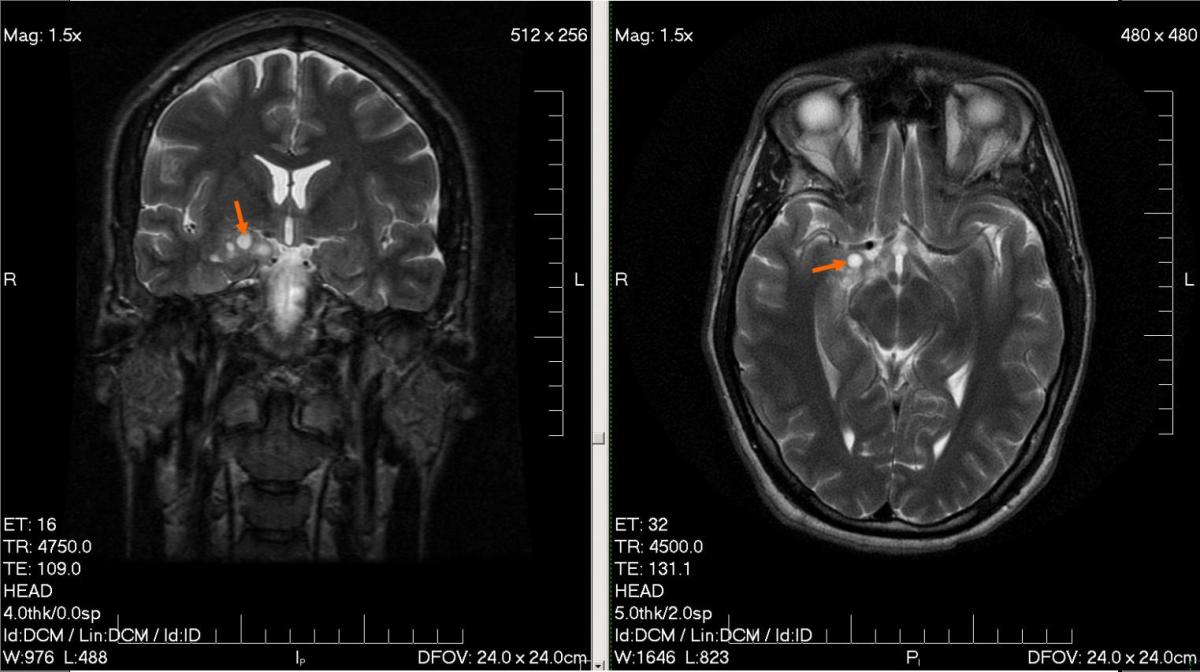

MRI_glioma_28_yr_old_male Publié 19 Mai 2014 à 1523 × 854 dans Cancer et téléphone portable : Les statistiques du doute